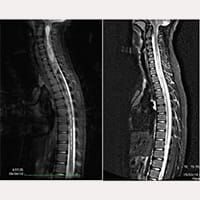

С октября 1993 года по июль 2017 года было произведено лечение с применением FILUM-SYSTEM® более 1000 пациентов, страдающих Синдромом натяжения спинного мозга и/или Заболеванием концевой нити с Синдромом Арнольда Киари I, Сирингомиелией и Сколиозом в различных диагностических комбинациях. В большинстве случаев достигнуто достаточное улучшение.